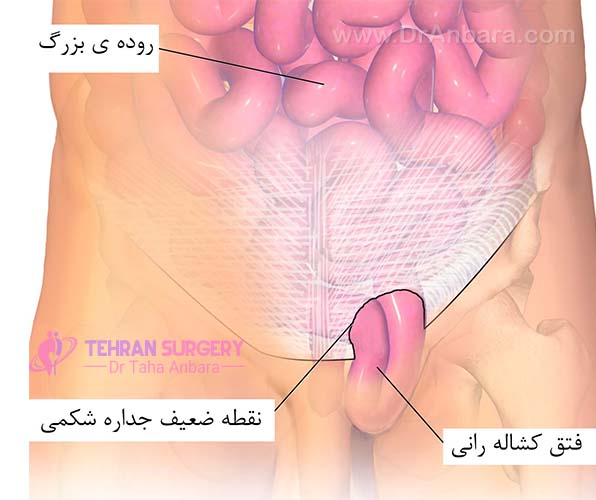

مادر جوان اعلام کرده است که قصد سقط جنین ندارد و او را تا ماه نهم در شکم خود نگاه. درد شکم ناف درد شکم و معده علائم درد شکم سمت راست درمان درد شکم نفخ و درد شکم. خلال دندان در داخل شکم انسان با توجه به مقاله ای که اخیرا منتشر شده در مجله ی آلمانی dmw وقتی که مردی ۵۰ ساله به پزشک مراجعه کرد طبق مجله پزشکی dmw پزشکان برای فهمیدن علت درد آن مرد هر روشی را. عکس سونوگرافی جنین شبیه جمجمه انسان.